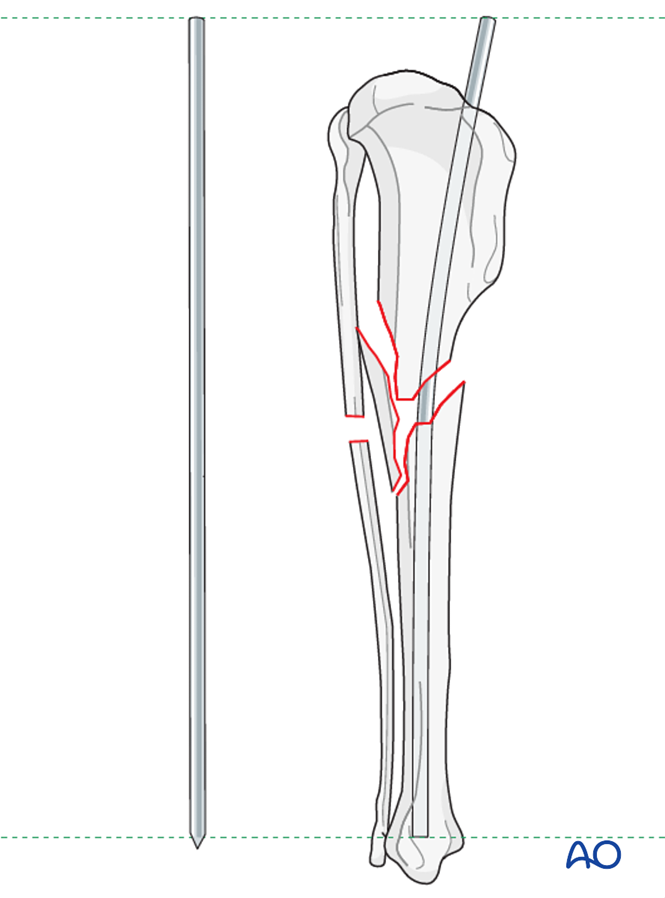

Anterolateral Tibial Bowing and Congenital Pseudoarthrosis of the Tibia ...

Frontiers | Anterolateral congenital tibial bowing: case report